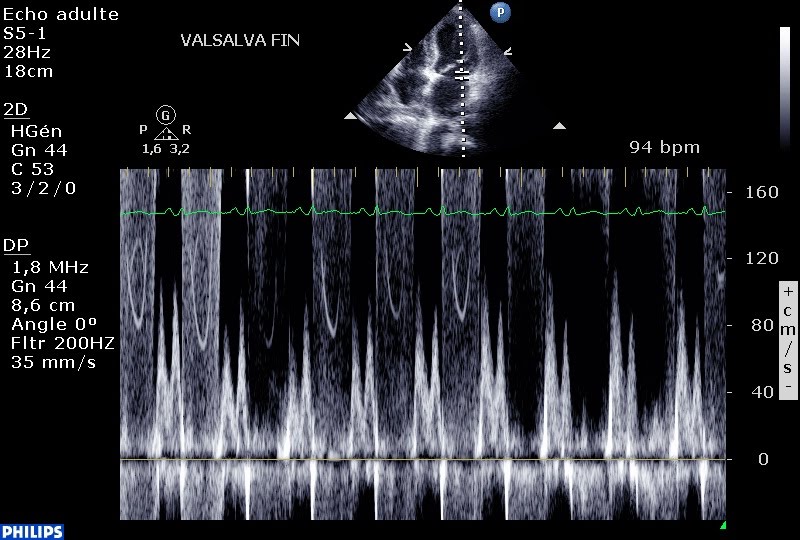

Etape 4 : lorsque le retour veineux augmente (le flux mitral inversé de l’étape 3 redevient restrictif à la droite de l’écran) , l’IM disparait à nouveau…